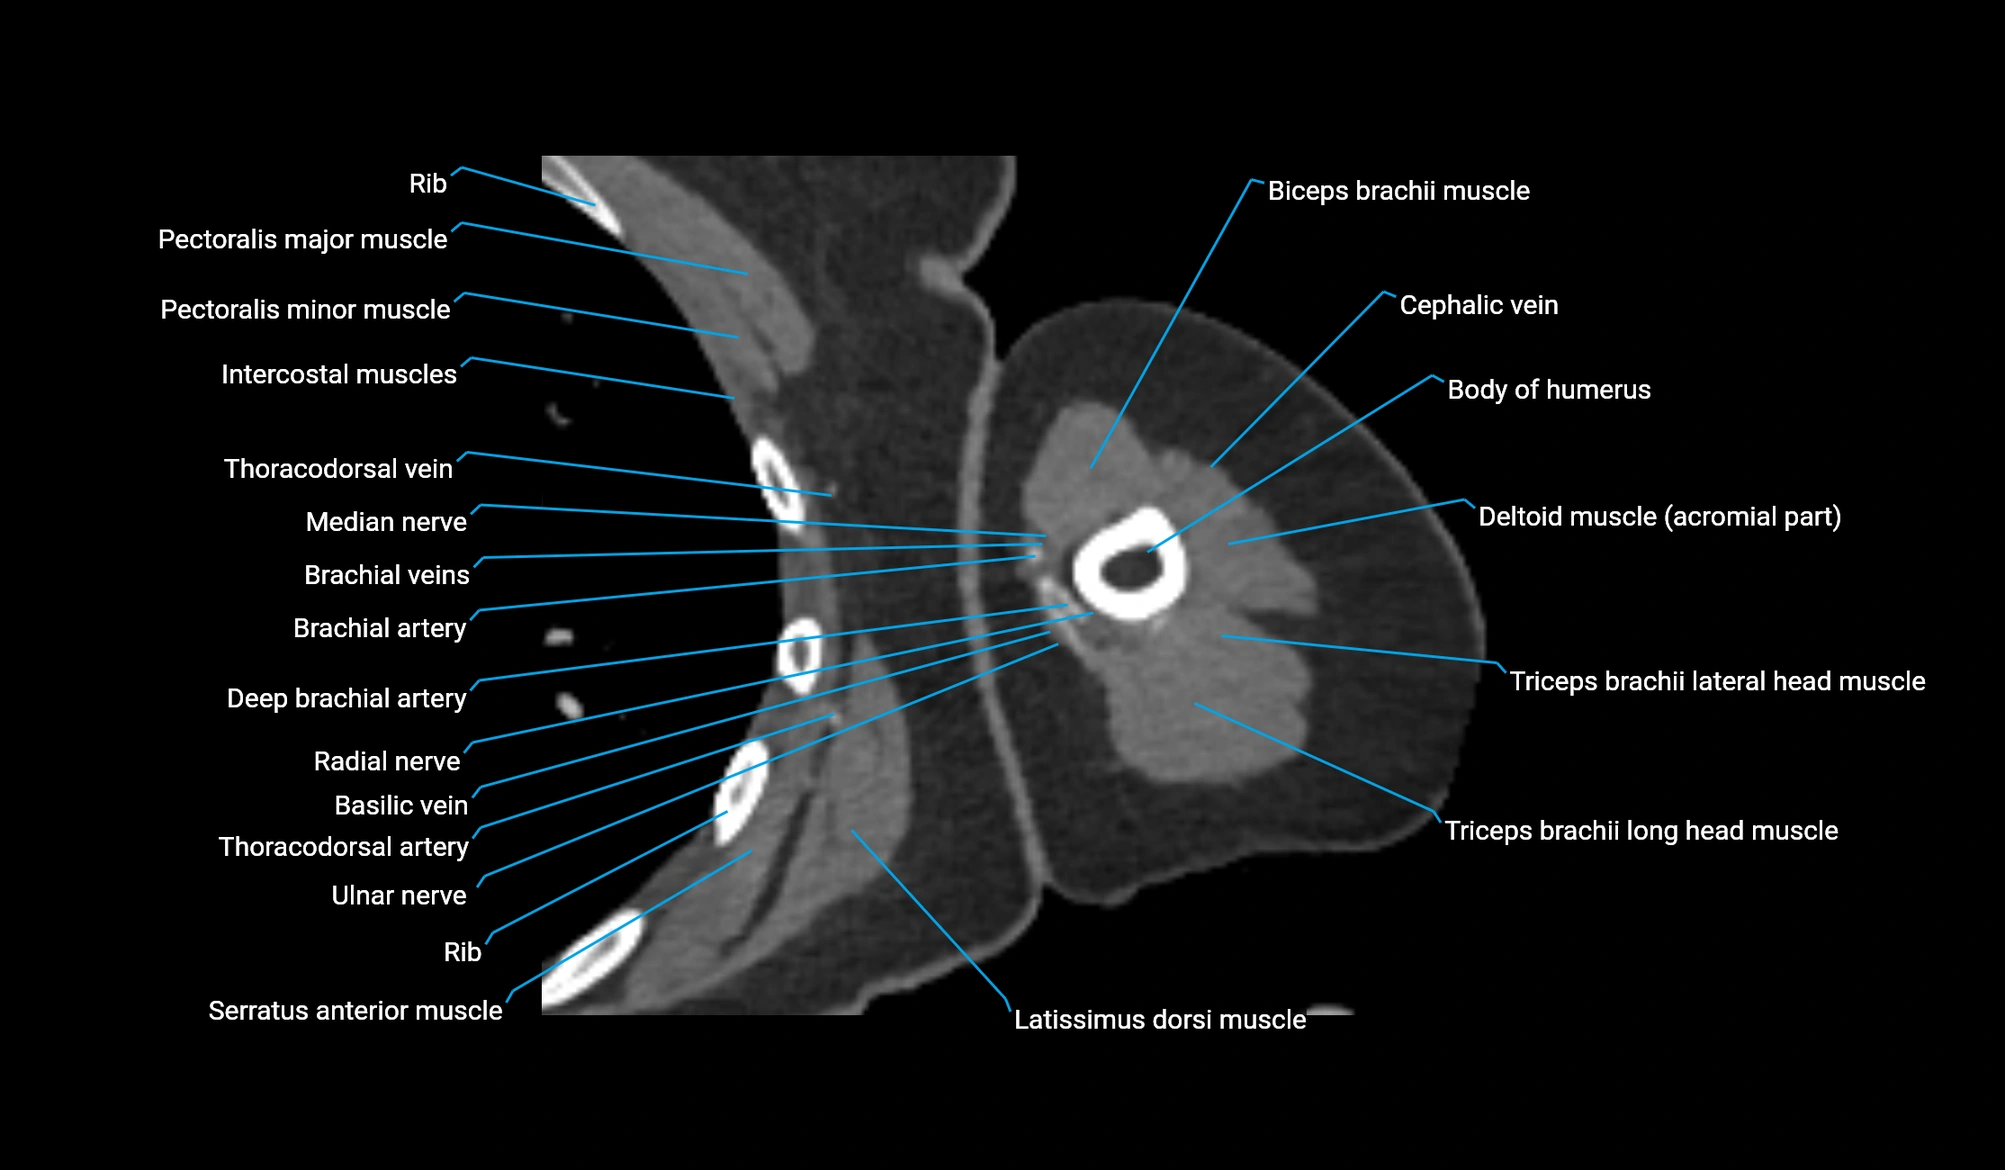

- Body of humerus

- Biceps brachii muscle

- Cephalic vein

- Brachialis muscle

- Deep brachial artery

- Brachial artery

- Basilic vein

- Ulnar nerve

- Median nerve

- Long head of triceps brachii muscle

- Lateral head of triceps brachii muscle

- Pectoralis major muscle

- Pectoralis minor muscle